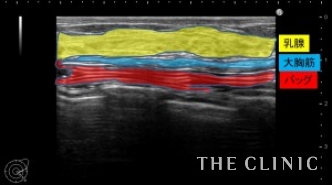

右は軽度のカプセル拘縮がありましたが、バッグの破損はありません。(画像左)

左はバッグは破損してほぼ完全に虚脱していました。(画像右)

乳房の下部にわずかに漏出したCMCが認められます。